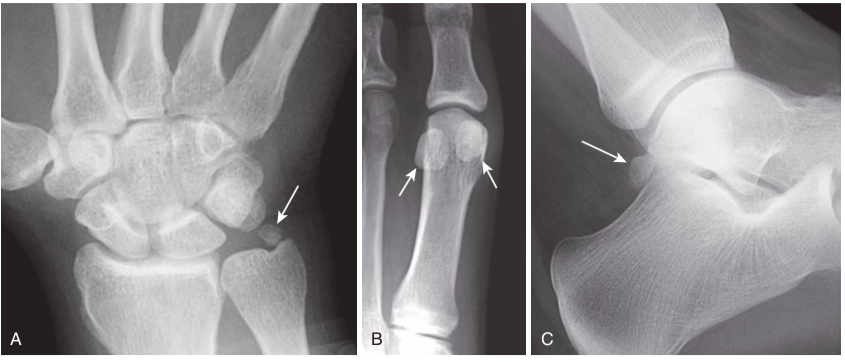

Pitfalls in fracture diagnosis.

A,Old, unhealed fracture fragments (whitearrow). B,Sesamoids (bones that form in a tendon as it passes over a joint) (whitearrows). C,Accessory ossicles (acces- sory epiphyseal or apophyseal ossification centers that do not fuse with the parent bone, such as this os trigonum;white arrow). These examples can sometimes mimic acute fractures. Unlike fractures, these small bones are corticated (i.e., there is a white line that completely surrounds the bony fragment), and their edges are usually smooth. Sesamoids and accessory ossicles are usually bilaterally symmetrical.